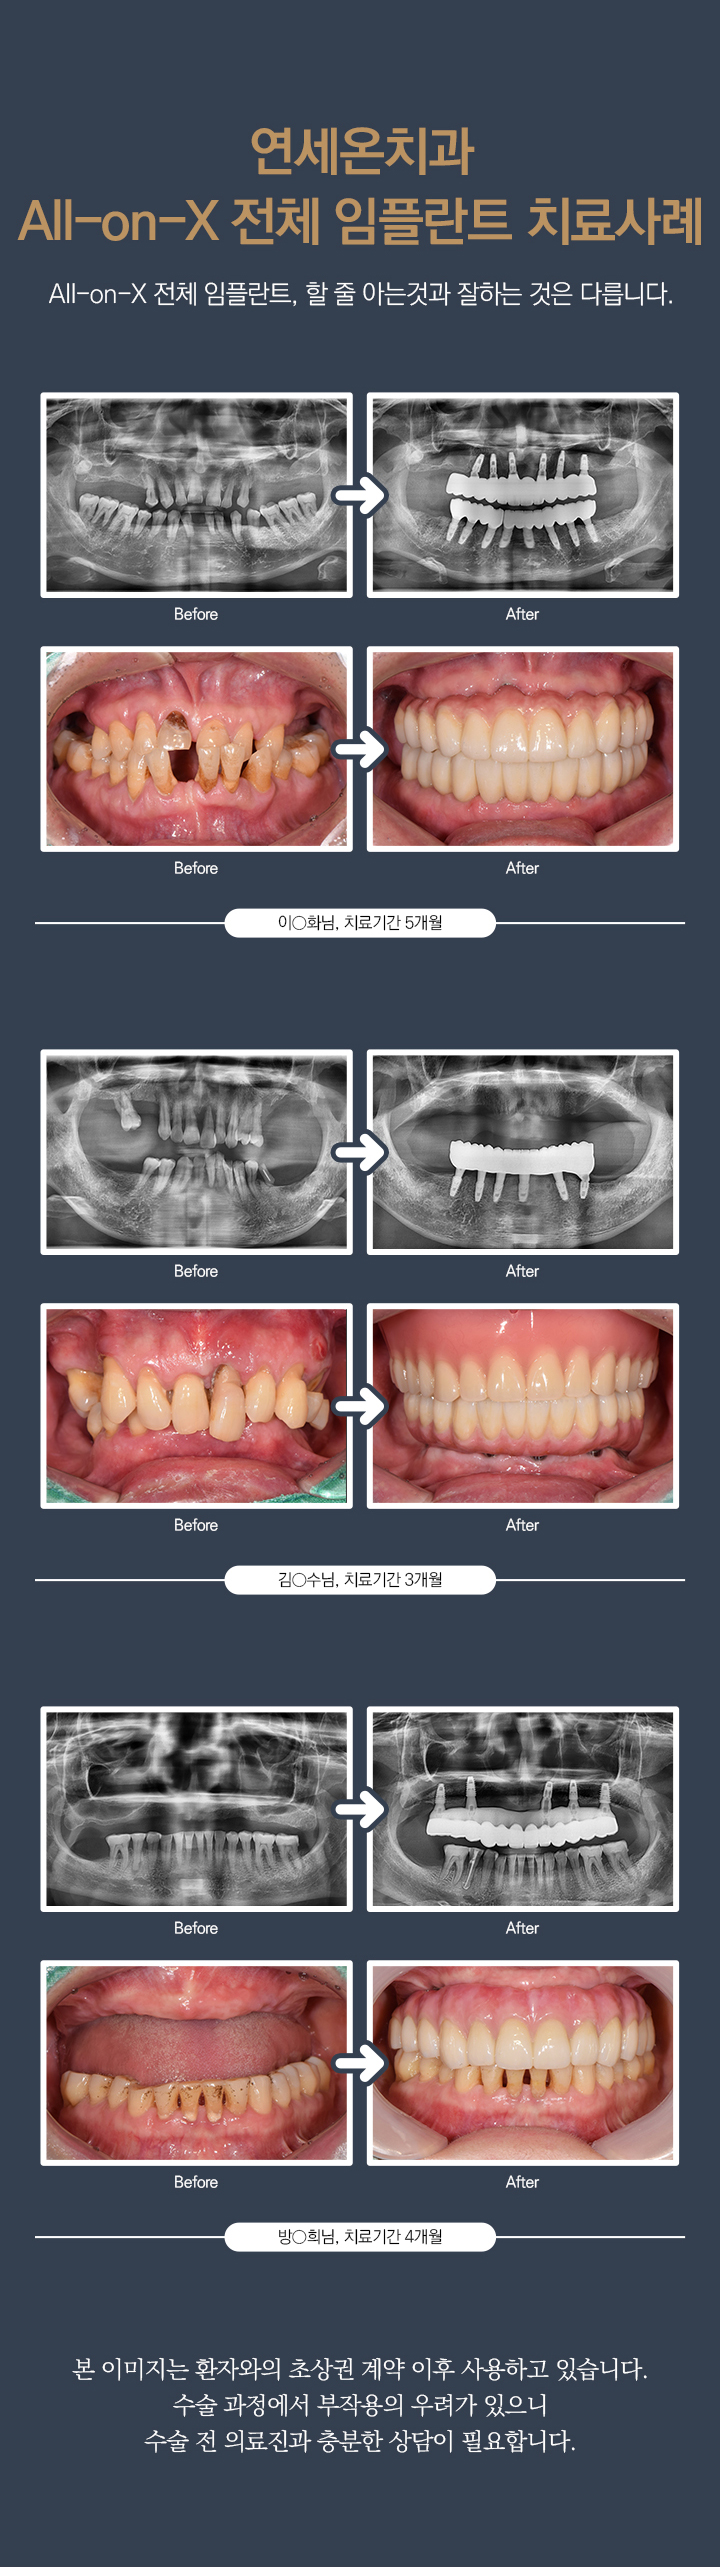

본 사진은 환자분의 동의하에 게재하였습니다.